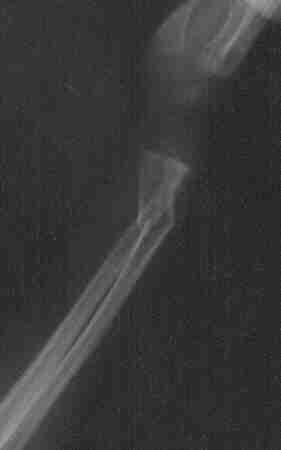

Fractura de muñeca

Fractura de muñeca izquierda. Pablo, 23 meses